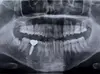

Les examens complémentaires

Des radios et des empreintes pourront être réalisées afin de venir judicieusement compléter l’examen clinique

Entre la première et la deuxième consultation, en votre absence, nous réalisons une étude approfondie de l’ensemble des éléments recueillis lors de l’examen clinique et des examens complémentaires. Cela nous permet de confirmer de façon précise le diagnostic de votre état dentaire.